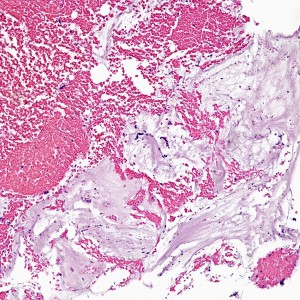

At low power, the majority of the specimen consists of decidua (square) and gestational-type endometrium (circle).